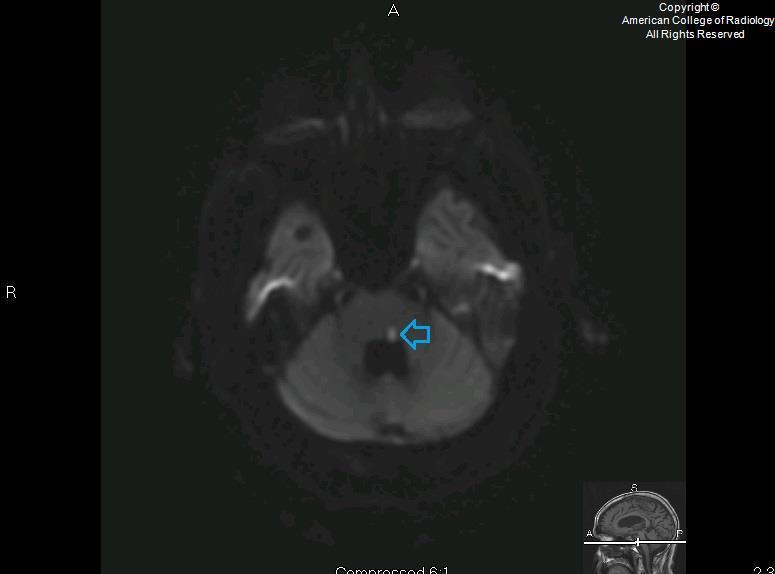

Facial colliculus syndrome